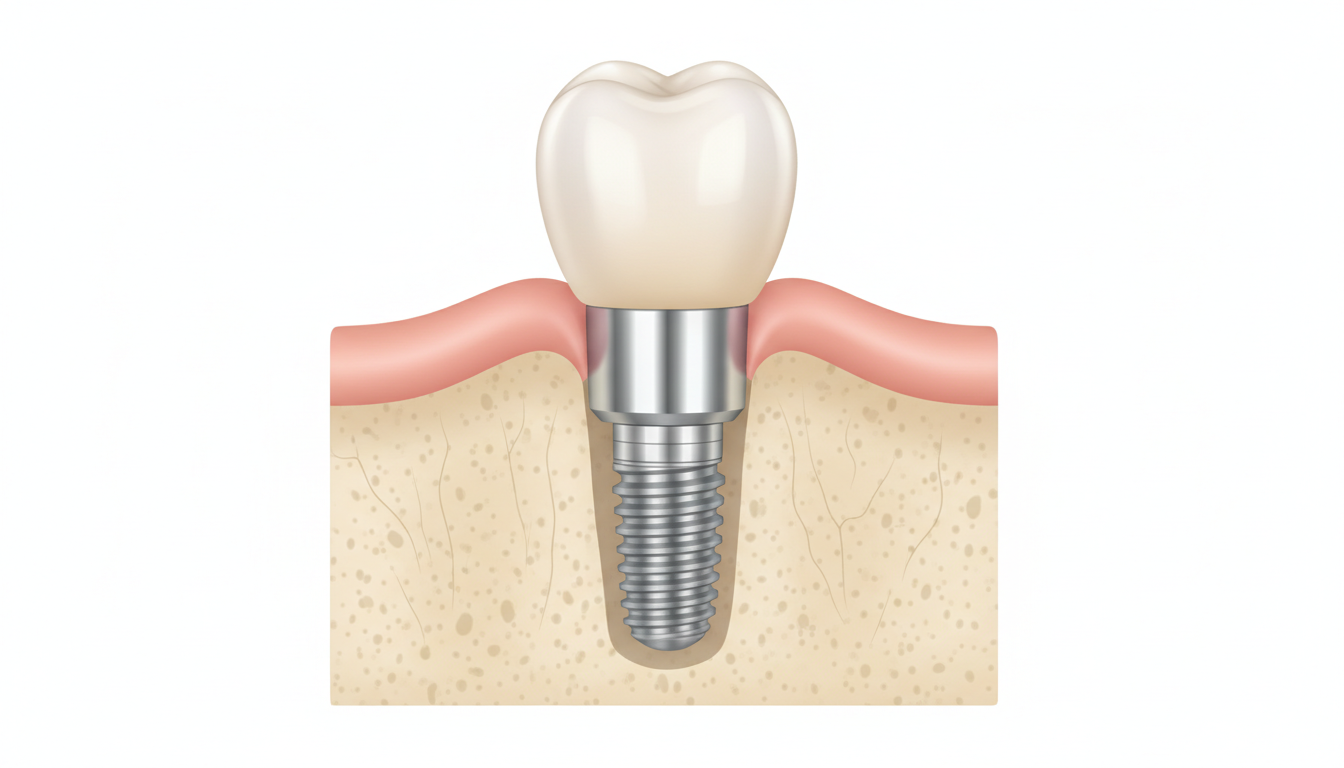

インプラント治療とは何か〜基本をおさらい

インプラント治療は、失った歯の根の代わりに人工の歯根を顎の骨に埋め込み、その上に人工歯を取り付ける治療法です。

インプラント体(人工歯根)、支台部(アバットメント)、人工歯の3つのパーツで構成されています。顎の骨にしっかりと固定されるため、天然歯に近い噛み心地が得られることが特徴です。

インプラント治療のメリット

- 天然歯に近い噛み心地・見た目が得られる

- 隣の歯を削る必要がない(ブリッジと異なる点)

- 顎の骨への刺激が伝わり、骨吸収を抑える効果が期待できる

- 取り外し不要で、日常生活での使いやすさが高い

インプラント治療の注意点

- 外科的な手術が必要になる

- 治療期間が数ヶ月単位になることが多い

- 顎の骨の量・質が不足している場合は追加処置が必要になることがある

- 全身疾患(糖尿病・骨粗しょう症など)によっては適応外になる場合がある

- 保険適用外の治療であるため、費用の負担が大きい

インプラント治療は、すべての方に適しているわけではありません。担当の歯科医師と十分に相談したうえで、ご自身の状態に合った治療法を選ぶことが大切です。